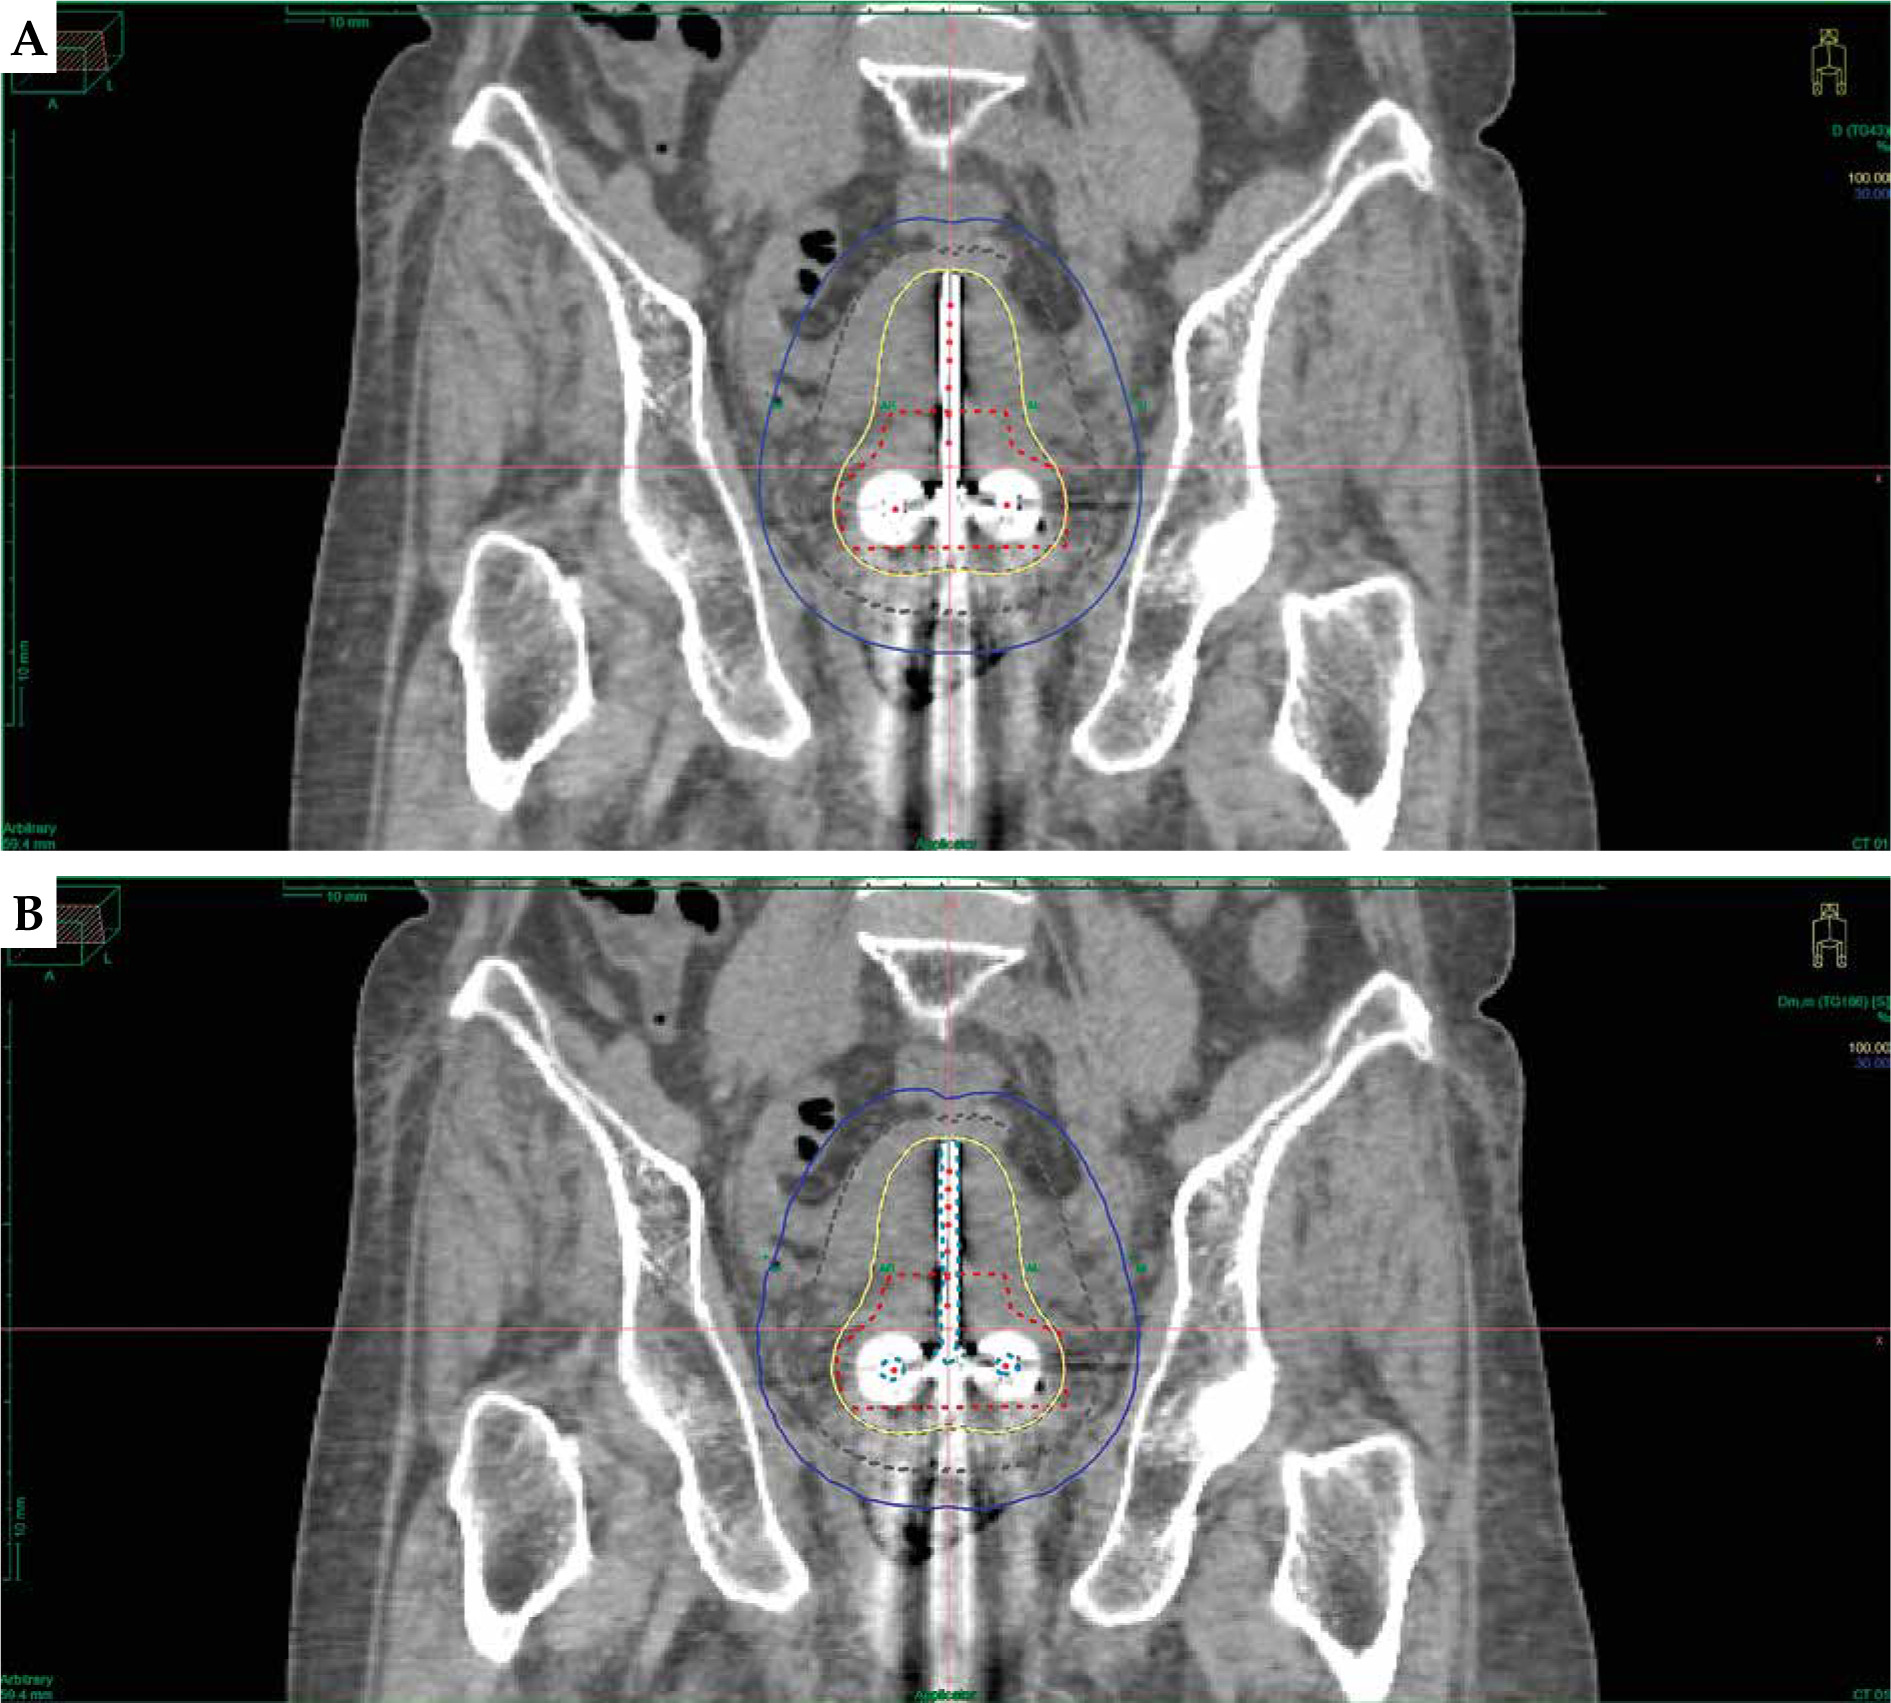

Treatment plans on TG-43 and ACE (TG-186) were made using Elekta Oncentra Brachy treatment planning system (OCB TPS) version 4.6.2. Initially, all plans were established based on the TG-43 formalism and subsequently normalized at point A, which was defined as a point 2 cm lateral to the central canal of the uterus and 2 cm up from the mucous membrane of the lateral fornix, in the axis of the uterus, according to the ICRU report 89 [11], followed by graphical optimization. Before performing ACE calculations, materials were assigned to delineated regions of interest (ROIs). Priority was given to overlapping structures, as indicated in Table 2. Material properties and associated mass densities were obtained from the AAPM TG-186 publication [4]. A set of 30 patients were re-planned using the TG-186 algorithm, maintaining the original dwell positions and dwell time without any adjustments, with 2.5 mm step size for all the plans. This process involved a step size of 2.5 mm for dwell positions for both the plans. A 3D dose grid setting of voxel size 110 × 150 × 150 mm was employed to delineate volume encompassed by 100% of prescribed isodose curve (IV100), and volume encompassed by 50% of prescribed isodose curve (IV50). A pear-shaped dose distribution of tandem and ovoid applicator for the TG-43 and TG-186 dose calculation algorithms are depicted in Figure 1.

The gradient index (GI), a plan quality index closely aligned with the focus of this study, characterizes the dose fall-off in both the TG-43 and ACE (TG-186) plans. Figure 2 illustrates the isodose gradient concerning HR-CTV target, bladder, rectum, and sigmoid. Notably, GI was 0.53% lower in the ACE (TG-186) plans compared with the TG-43 plans. This difference can be attributed to dose attenuation resulting from applicator materials, air gaps, and soft tissues, as the TG-43 algorithm assumes homogeneity throughout the entire CT dataset, treating it as a uniform water phantom.